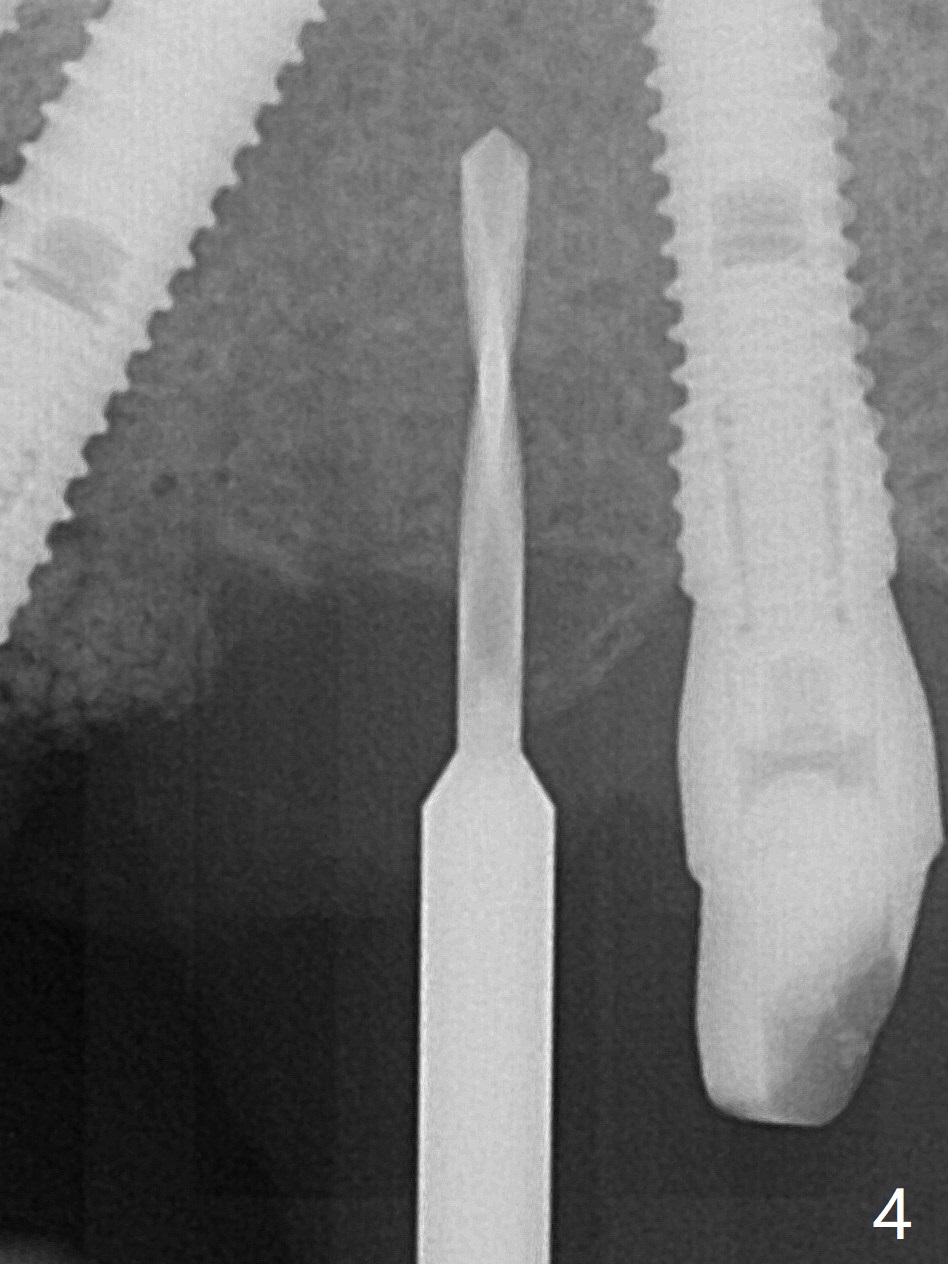

A 48-year-old man returns to clinic with fractured FPD 1 year 5 months post cementation (temp bond, Fig.1,7). It appears necessary to add an implant at #13 site (Fig.2). The narrow ridge is reduced to start an osteotomy (Fig.3 *). After change in osteotomy position and trajectory (Fig.4), a 3x10(4) mm 1-piece implant is placed (Fig.5). With deeper placement of the implant (Fig.6 arrow), cortical bone graft is placed (*).